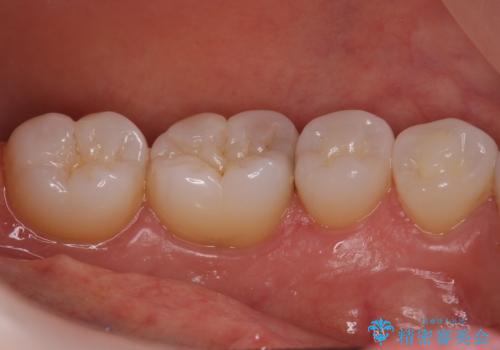

奥歯の虫歯 セラミックインレーでの治療

- 奥歯の黒ずみが気になるとのことで来院されました。

検査の結果、歯と歯の間に小さな虫歯ができていることが確認できました。

白い詰め物をご希望されたため、今回はセラミックインレーでの治療となりました。

黒ずみもなくなり、虫歯も取り切ることができ大変満足していただけました。

虫歯の除去後に適合の良い修復物を装着することは今後の虫歯リスクを減らすことに繋がります。